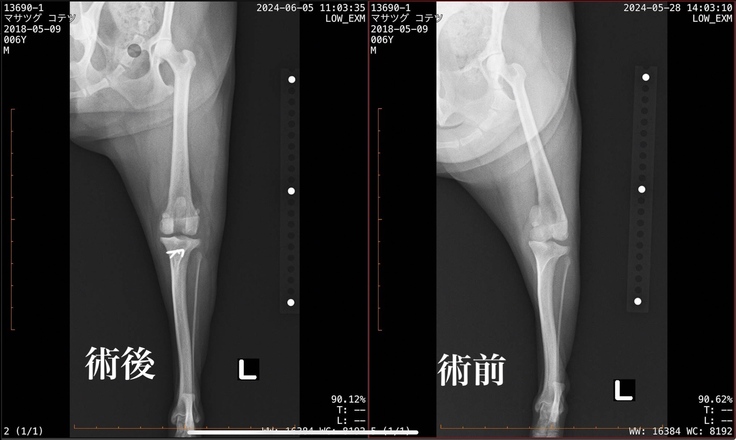

こてつは右膝:グレード4に近い3 左膝:3の診断でした。右膝の症状がこれ以上ひどくならないようにと右膝の手術を行いました。

・前の右膝の手術で挿入したピンが通常は内側に向けて挿入されるべきものが、外側に向けて挿入されているため機能しておらず、触るとクルクルと回ってしまう状態。そのため一度手術した場所も再度手術が必要。

手術は無事に最高しましたが再手術となった右側に関しては、元々入っていたピンのせいで骨が脆くなっている状態でワイヤーも使って固定をしなければなりませんでした。

また役割を果たしていなかったピンが皮下で組織を刺激し、軟組織が過剰に増えている状態でありその組織も切除が必要だったそうです。

(術前後レントゲン)